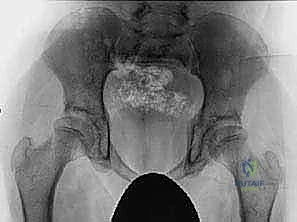

الخطر الصامت: ماذا يحدث إذا تم إهمال العلاج؟

يؤكد الأستاذ الدكتور محمد هطيف دائمًا أن "الوقت هو العامل الحاسم في جراحة عظام الأطفال". إهمال علاج تشنجات العضلة الحرقفية القطنية والعضلات المقربة يؤدي إلى سلسلة من المضاعفات الكارثية:

- الخلع الجزئي والكامل للورك (Hip Subluxation and Dislocation): القوة المستمرة للعضلات المتشنجة تسحب رأس عظمة الفخذ تدريجيًا خارج التجويف. إذا حدث الخلع الكامل، تصبح الجراحة أكثر تعقيدًا بكثير (تتطلب قطع العظام وإعادة توجيهها).

التشخيص الدقيق: المعيار الذهبي في عيادة الأستاذ الدكتور محمد هطيف

يبدأ العلاج الناجح بتشخيص دقيق لا يقبل الخطأ. يتمتع الأستاذ الدكتور محمد هطيف بخبرة تتجاوز العشرين عامًا في تقييم حالات العظام المعقدة للأطفال. يشمل التقييم:

- الفحص السريري الشامل: استخدام اختبارات طبية متخصصة مثل "اختبار توماس" (Thomas Test) لتقييم تشنج العضلة الحرقفية القطنية، واختبار زاوية التبعيد لتقييم العضلات المقربة.

- تحليل المشي (Gait Analysis): مراقبة دقيقة لكيفية حركة الطفل وتوزيع وزنه.

- الأشعة السينية (X-rays): لتقييم وضعية رأس عظمة الفخذ داخل التجويف الحُقي وحساب "مؤشر رايمرز" (Reimers Migration Percentage).

- الأشعة المقطعية ثلاثية الأبعاد (3D CT Scans): في الحالات المتقدمة، تُستخدم لتقييم التشوه العظمي بدقة متناهية قبل التخطيط للجراحة.